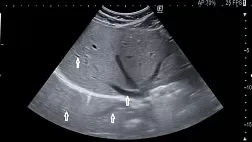

Комментарии: Эндоскопическая шкала EREхFS (приложение Г3, приложение А3, рисунки 1, 1а, 1б,1в,1г,1д), оценивает 5 главных эндоскопических признаков ЭоЭ (Edema-отек, Rings-кольца, Exudates-экссудат, Furrows-борозды, Strictures-стриктуры) в баллах [33,118,119,120,121,188]. У 10=25% пациентов с ЭоЭ при эндоскопии пищевода видимых патологических изменений не определяется [117], в связи с чем эндоскопическое исследование пищевода не может служить единственным критерием установления диагноза ЭоЭ без патологоанатомического исследования биоптатов из пищевода [122,123]

Комментарии: Рентгеноскопия пищевода с контрастированием в диагностике ЭоЭ является дополнительным методом, позволяющим с высокой точностью выявить проксимальные и дистальные стриктуры пищевода, оценить их протяженность, диаметр пищевода в месте сужения, принять решение о необходимости баллонной дилатации стеноза пищевода или бужирования пищевода (приложение А3:рисунок 3) [120,128,129].